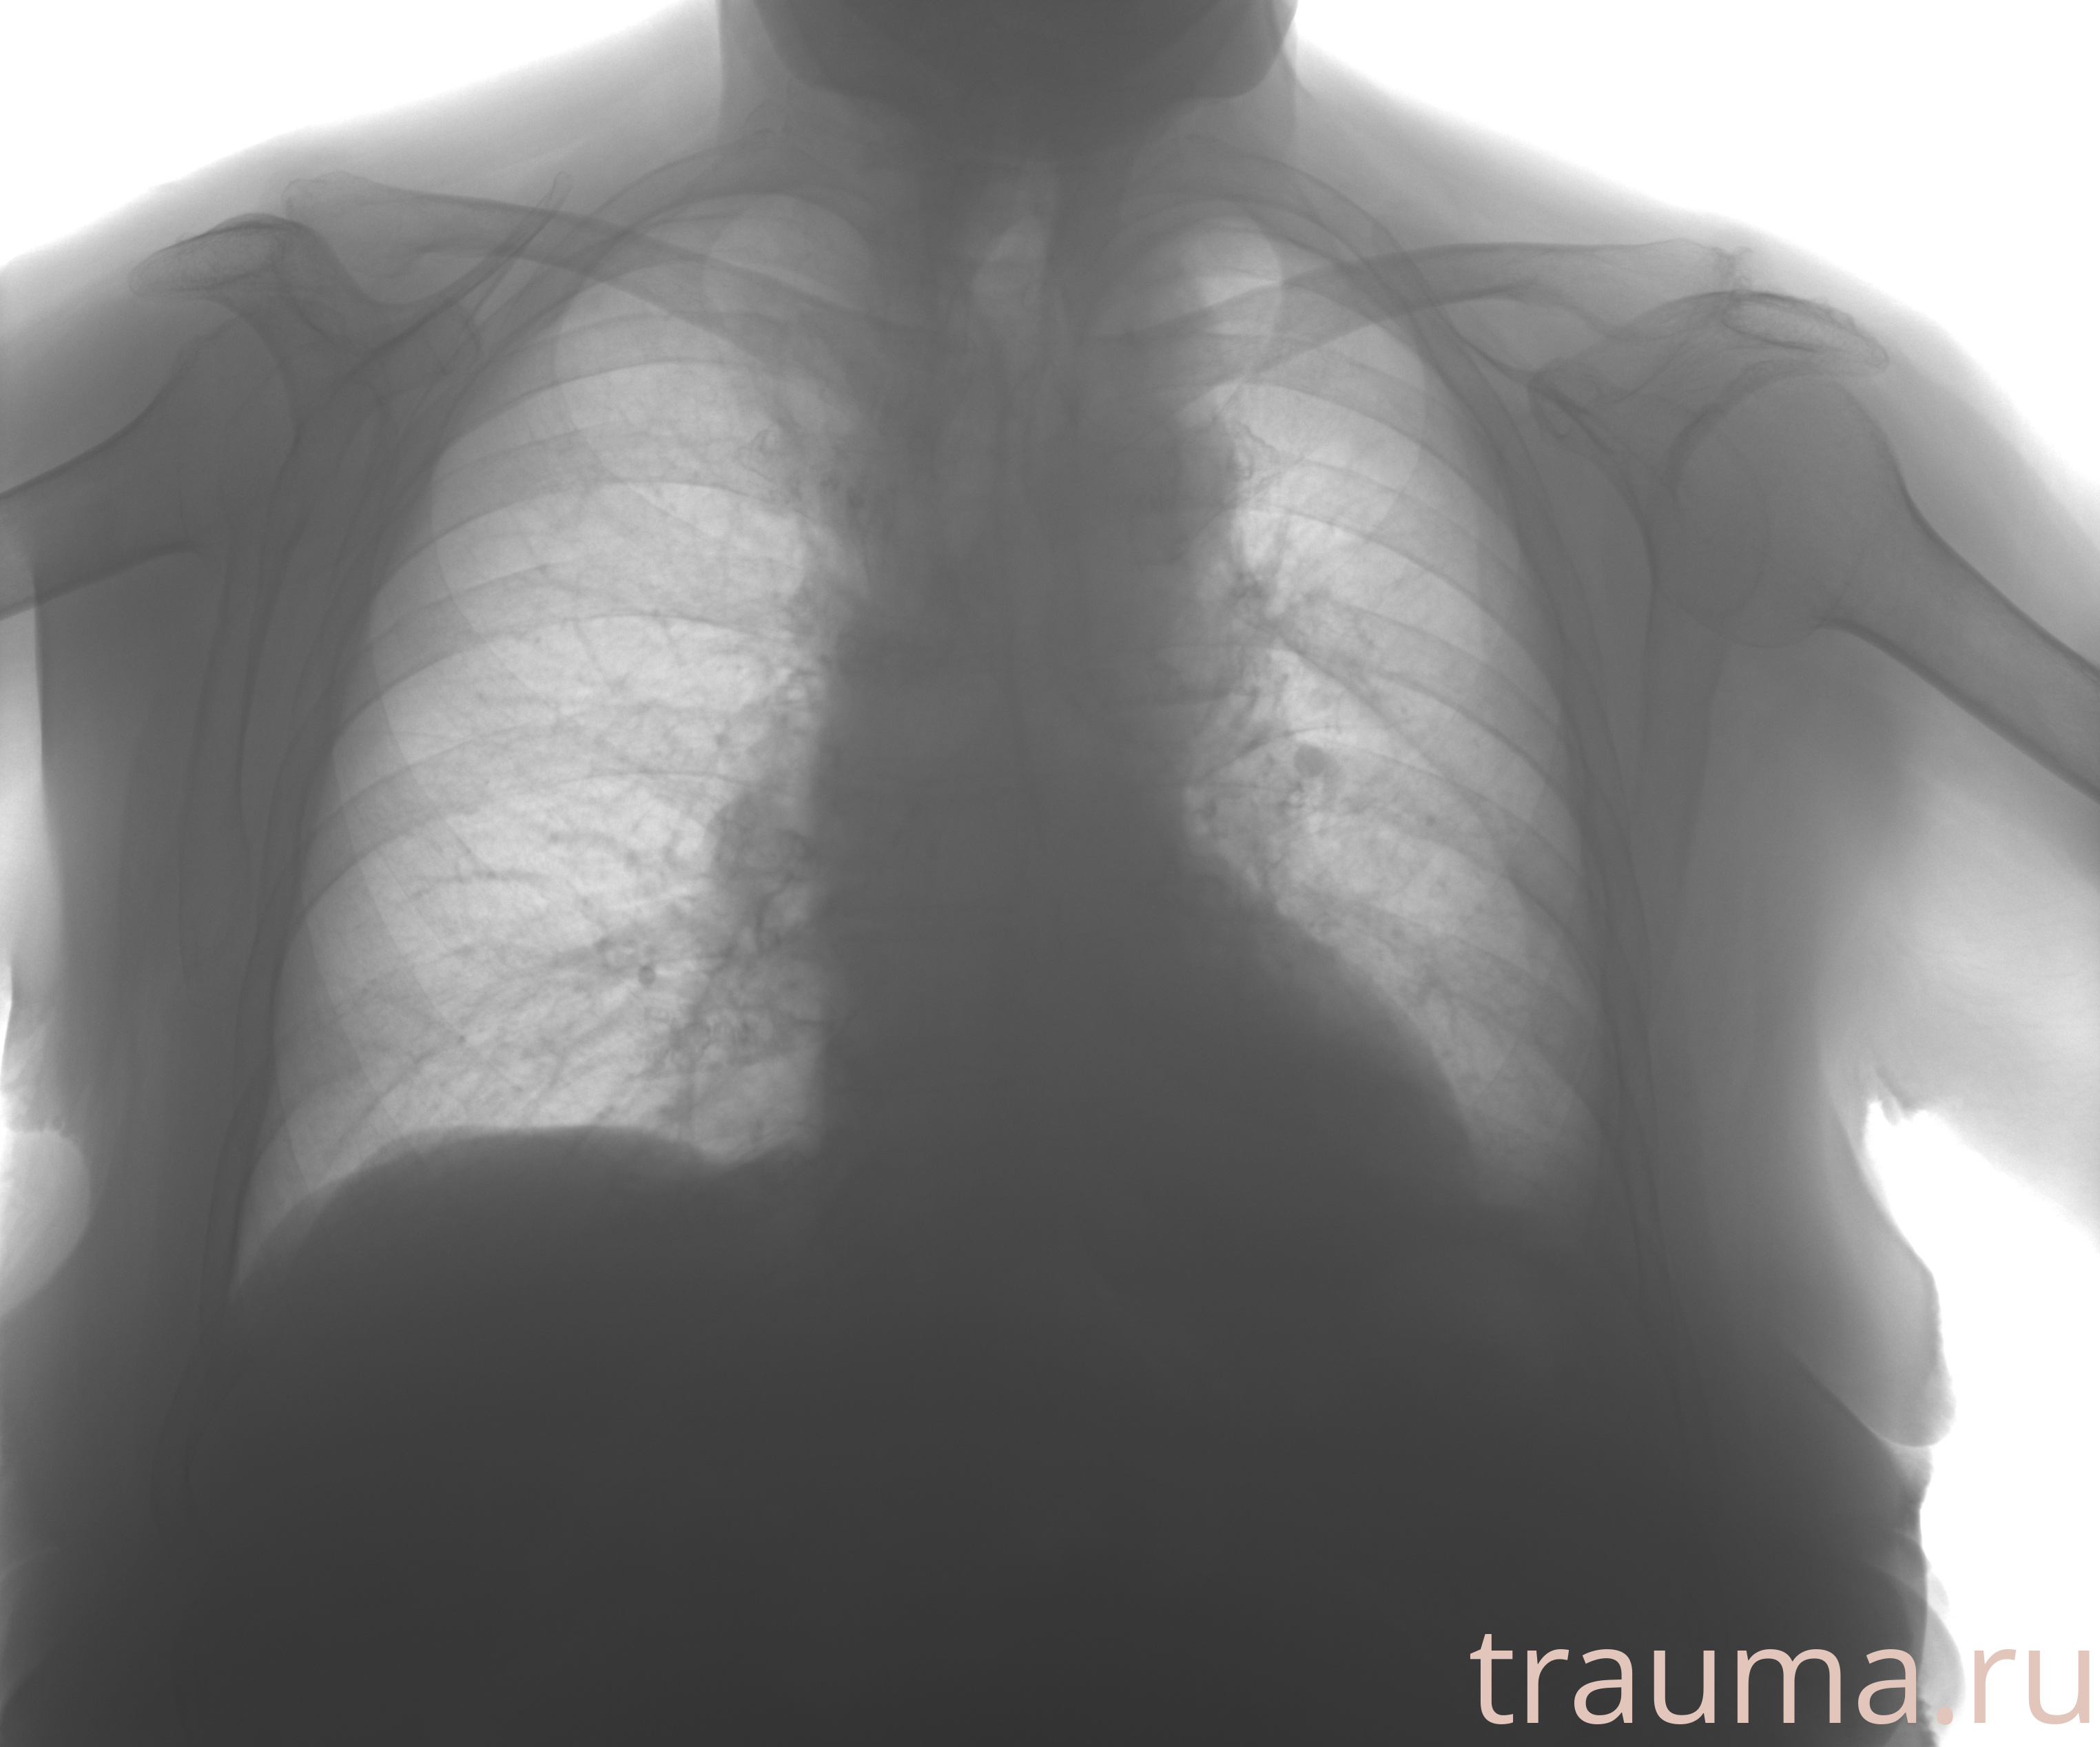

Рентгенограммы

Рентген на дому: по вашему адресу приезжает врач-рентгенолог, травматолог-ортопед с мобильным рентгеновским аппаратом, проводит диагностику травмы или заболевания, делает необходимые рентгенограммы, дает рекомендации по дальнейшему лечению. Получить качественные снимки в домашних условиях возможно благодаря уникальной методике, разработанной МосРентген Центром для института  Склифосовского

Яркость: 1   Контраст: 1   Инвертировать: 0 Увеличение: 1

Перетаскивайте мышь вверх/вниз для контраста, влево/право для яркости. Прокрутка колесом изменяет масштаб. Нажмите Сбросить для возврата к исходному изображению. При увеличении держите мышь в той области, которую хотите рассмотреть.